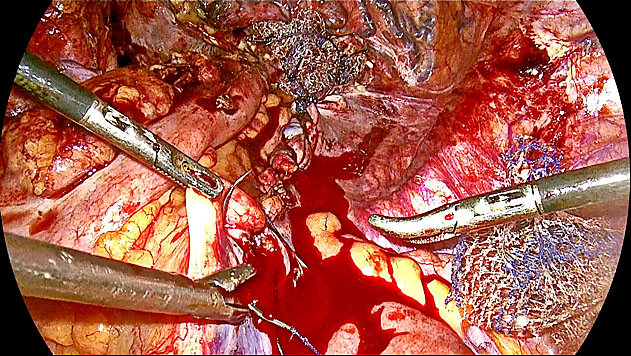

Laparoscopic correction of vault prolapse begins with anterior dissection using a vaginal probe or malleable retractor to elevate the bladder up to the bladder neck. Posteriorly, the rectovaginal space is entered, and the levator ani muscles are identified bilaterally. A Y-shaped mesh is positioned with its central portion anchored to the vaginal vault using 4–5 sutures anteriorly and posteriorly, while the lateral arms are secured to the levator ani muscles. The mesh is then covered with peritoneum to prevent mesh exposure, bowel adhesions and obstruction. At the sacral promontory, tackers are placed just below the curvature to avoid the median sacral vessels and minimize the risk of injury to intervertebral discs at higher levels. Intraoperative ureteral injury, although rare, may necessitate immediate reconstruction. When adequate ureteral length is available, a uretero-ureteral anastomosis can be performed using four interrupted 4–0 or 5–0 non-absorbable or delayed-absorbable sutures over a double-J (DJ) stent. For distal ureteral injuries, ureteroneocystostomy is the preferred approach (Figure 14). The ureter is fish-mouthed to enlarge its opening and anastomosed to a freshly created cystotomy, typically at the 5 or 7 o’clock position on the bladder dome. A DJ stent is inserted to ensure patency. When tension is anticipated at the anastomosis site, ureterovesical implantation with psoas hitch is indicated. This involves mobilizing the bladder through dissection of the space of Retzius and anchoring it to the psoas muscle to reduce tension. The ureter, ligated above the injury site, is brought into the bladder through a small cystotomy. It is stabilized with anchoring sutures to the bladder wall, and mucosa-to-mucosa anastomosis is performed at the 6, 3, 9 and 12 o’clock positions. A DJ stent is placed, and the bladder is closed in two layers. To date, we have successfully performed six ureterovesical reimplantations. Nevertheless, meticulous surgical technique to prevent ureteral injury remains paramount, as prevention is always preferable to repair.

14

Sequential steps for laparoscopic surgery for vault prolapse. A. Mobilization of the left ureter from surrounding tissue. B. Bladder mobilization to allow upward movement for tension-free anastomosis. C. Psoas hitch: bladder is sutured to the ipsilateral psoas muscle to bring it closer to the ureter. D. Creation of a new cystotomy (bladder opening) at the 7 o’clock position for ureteral reimplantation. E. Ureter is pulled into the bladder, a small ureterotomy is made, and anastomosis begins with mucosa-to-mucosa suturing; a DJ stent is inserted. F. Completion of bladder closure after ureteroneocystostomy.

Ureteric injuries can vary in both location and extent, occurring near the bladder, at the pelvic brim, or involving significant segmental loss. For injuries close to the bladder, laparoscopic ureterovesical implantation is typically performed over a ureteric or DJ stent. This involves fish-mouthing and freshening the distal end of the ureter to ensure an optimal connection with the bladder. In cases of significant ureteric segment loss, the bladder is mobilized, and the ureter dissected to allow a psoas hitch, which relieves tension on the ureter. Ureterovesical implantation with a DJ stent, typically left in place for 6 weeks, is recommended in such cases (Figure 14). For minor injuries located at the pelvic brim, a uretero-ureteric anastomosis over a stent is a viable and effective option.